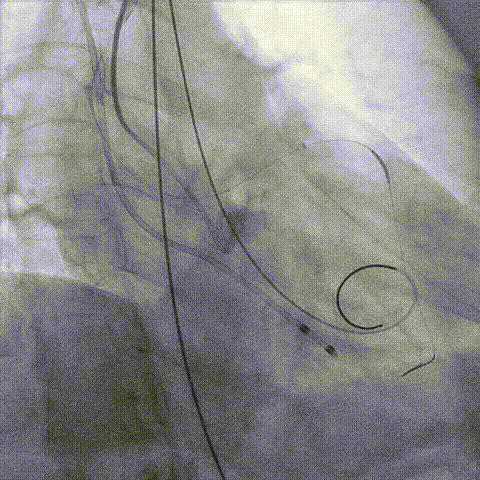

第一次释放

再次评估左冠开口,考虑调整瓣膜深度

回收后调整深度,再次释放

评估左冠开口

左冠开口切线位造影

决定左冠烟囱支架保护冠脉

调整支架位置

释放冠脉支架

释放瓣膜

造影评估

支架内后扩张

冠脉造影

根部造影